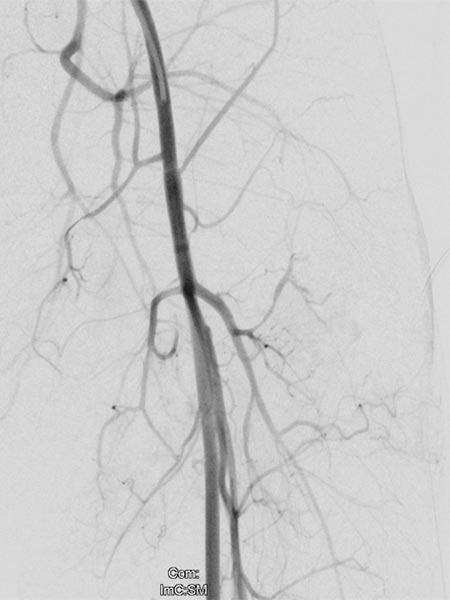

Weitere Tumorgefäße mit blush-artigem, diffusem Enhancement, typisch für Gefäßtumor/NICH. All diese Gefäße müssen selektiv embolisiert werden um eine Involution zu induzieren.

Weitere selektive Partikelembolisation. Die mit Kontrastmittel gemischten Embolisationspartikel verbleiben in den Tumorgefäßen.